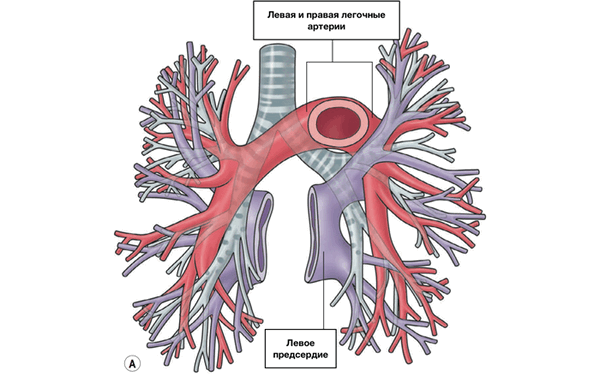

Кровоснабжение легких

Легкие кровоснабжаются как из легочной, так и из бронхиальной артерий. Кровоснабжение из легочной артерии осуществляется в соответствии с ветвлением бронхов, из бронхиальной артерии кровоснабжаются воздухоносные пути, висцеральная плевра и лимфоидная ткань.

Сосуды и нервы легких. Артериальная кровь для питания легочной ткани и стенок бронхов поступает в легкие по бронхиальным ветвям из грудной части аорты. Кровь от стенок бронхов по бронхиальным венам оттекает в притоки легочных вен, а также в непарную и полунепарные вены. По левой и правой легочным артериям в легкие поступает венозная кровь, которая в результате газообмена обогащается кислородом, отдает углекислоту и становится артериальной. Артериальная кровь из легких по легочным венам оттекает в левое предсердие. Лимфатические сосуды легких впадают в бронхолегочные, нижние и верхние трахеобронхиальные лимфатические узлы.

Начинается в правом желудочке, выбрасывающем венозную кровь в лёгочный ствол. Лёгочный ствол делится на правую и левую лёгочные артерии. Лёгочные артерии ветвятся на долевые, сегментарные и субсегментарные артерии. Субсегментарные артерии делятся на артериолы, распадающиеся на капилляры. Отток крови идет по венам, которые собираются в обратном порядке и в количестве четырёх штук впадают в левое предсердие, где заканчивается малый круг кровообращения. Кругооборот крови в малом круге кровообращения происходит за 4—5 секунд.

Из капилляров легкого начинаются венулы, которые сливаются в более крупные вены и в каждом легком формируют по две легочные вены.

Из двух правых легочных вен больший диаметр имеет верхняя, так как по ней оттекает кровь от двух долей правого легкого (верхней и средней). Из двух левых легочных вен больший диаметр имеет нижняя вена. В воротах правого и левого легких легочные вены занимают их нижнюю часть. В задней верхней части корня правого легкого расположен главный правый бронх, кпереди и книзу от него — правая легочная артерия.

У левого легкого сверху находится легочная артерия, кзади и книзу от нее — левый главный бронх. У правого легкого легочные вены лежат ниже артерии, следуют почти горизонтально и на своем пути к сердцу располагаются позади верхней полой вены, правого предсердия и восходящей части аорты. Обе левые легочные вены, которые несколько короче правых, находятся под левым главным бронхом и направляются к сердцу также в поперечном направлении, кпереди от нисходящей части аорты. Правые и левые легочные вены, прободая перикард, впадают в левое предсердие (их конечные отделы покрыты эпикардом).